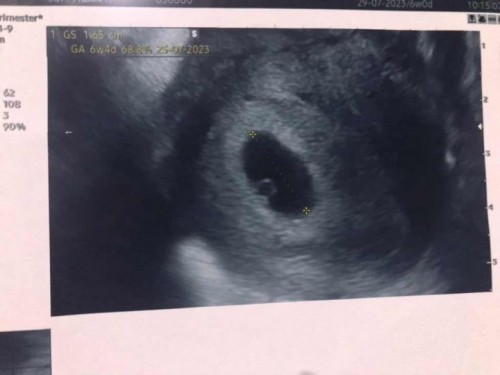

ถามแม่ๆหน่อยค่ะ วันนี้ไปซาวด์ท้องมาอายุครรภ์ในจออยู่ที่ 6w ซาวด์ไม่เจอตัวน้อง ไม่เจอหัวใจ คุณหมอบอกเจอแต่ถุงอ่อนที่เป็นแหล่งอาหารของน้องค่ะ ท้องแรกเคยท้องลม แม่ๆคิดว่าท้องนี้มีหวังจะเจอน้องไหมค่ะ แล้วแม่ๆซาวด์เจออะไรบ้างตอน6wค่ะ #ขอบคุณล่วงหน้านะคะ

5-6 วีค เจอแค่ถุงตั้งครรภ์เพราะน้องยังตัวเล็ก หมอจะอัลตร้าซาวด์ทางช่องคลอด ประมาณ 8 วีค ขึ้นไปถึงเจอน้องค่ะ เราเจอน้องตอน 8 วีค 6 d อัลตร้าซาวด์ผ่านหน้าท้อง

บ้านนี้ไปฝาก4wซาวด์ไม่เจออะไร 6wเจอแค่ถุงการตั้งครรภ์ค่ะ 8w3dถึงเจอน้องพร้อมหัวใจ ตอนนั้นหมอนัดซาวด์ทุก2สัปดาห์

บ้านนี้ซาวด์ตอนเเรก5วีคเจอเเค่ถุงกับไข่เเดงค่ะ หมอนัดอีกที8wเจอตัวน้องเเละหัวใจ

เราไปฝากตอน5วีคเจอแต่ถุง เจอตอน8-9วีคเป็นตัวและหัวใจเลยค่ะแม่ ทำใจให้สบายค่ะ